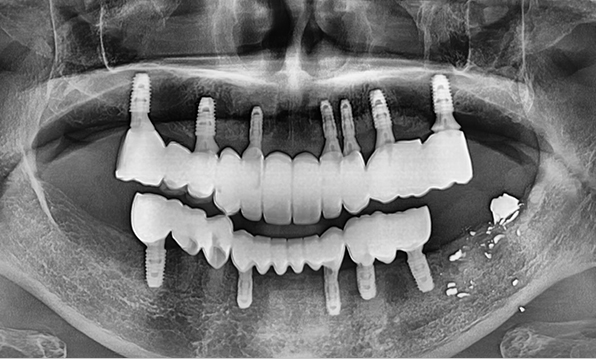

잇몸뼈가 얇은 상태

-

잇몸뼈 충분히 이식 후 임플란트 식립

성공을 위한 노하우, 잇몸뼈 재건 기술

전체 임플란트를 해야하는 환자들은

대부분 고령의 환자들로 오랜 틀니 사용

또는 노화로 인해 치조골이

거의 남아있지 않는 경우가 많습니다.

이 때, 치조골 이식을 병행하여 잇몸뼈 재건 후 안정적인 임플란트 식립을 하고 있습니다.

치료기간 : 2021.04.12~2021.09.15